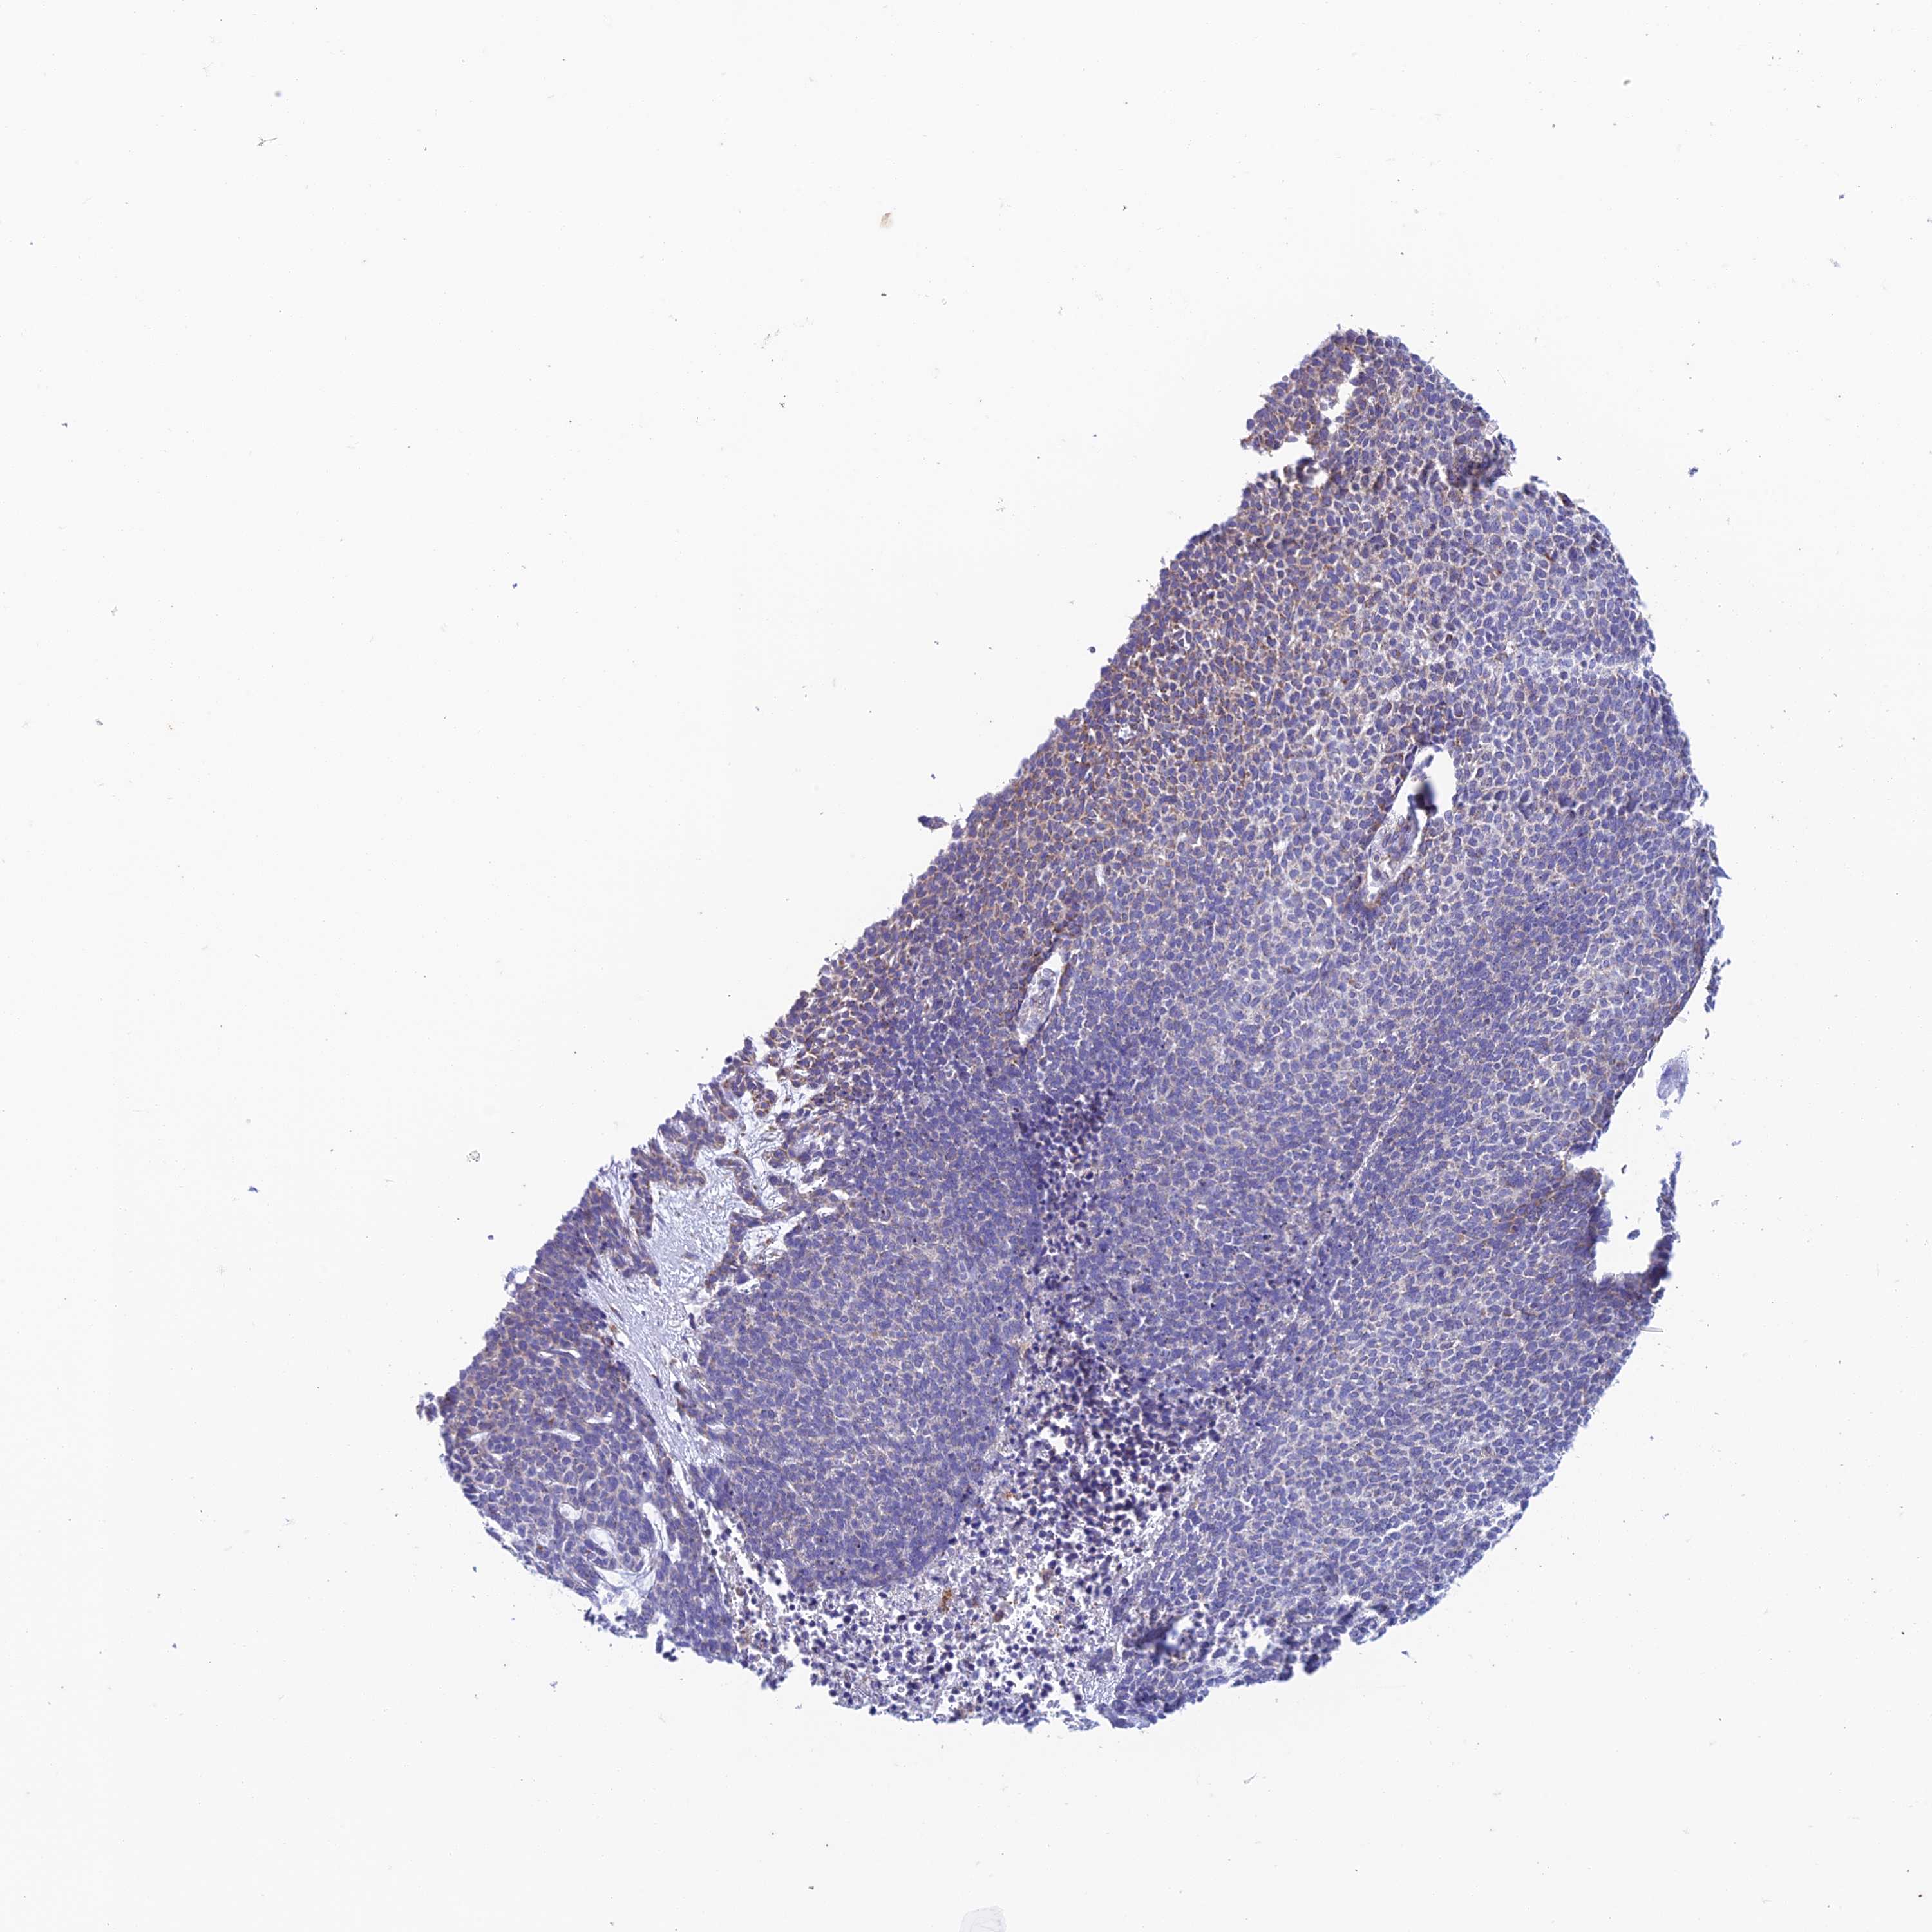

SKIN CANCER - Protein expressioni

A mouse-over function shows sample information and annotation data. Click on an image to view it in a full screen mode. Samples can be filtered based on level of antibody staining by selecting one or several of the following categories: high, medium, low and not detected. The assay and annotation is described here.

Each image is clickable and will lead to virtual microscopy that enables deeper exploration of all samples and also displays staining intensity scores, fraction scores and subcellular localization as well as patient and tissue information for each sample.

Antibody HPA043701

Squamous cell carcinoma, NOS